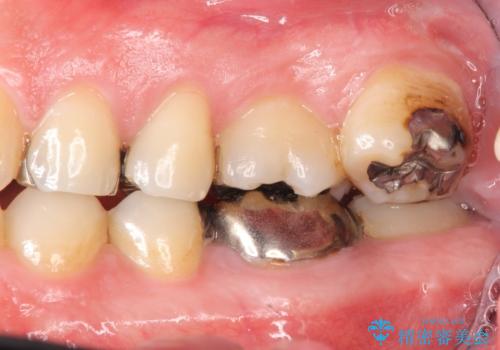

- 治療中は歯磨きがしにくくなるため、虫歯や歯周病になりやすくなります